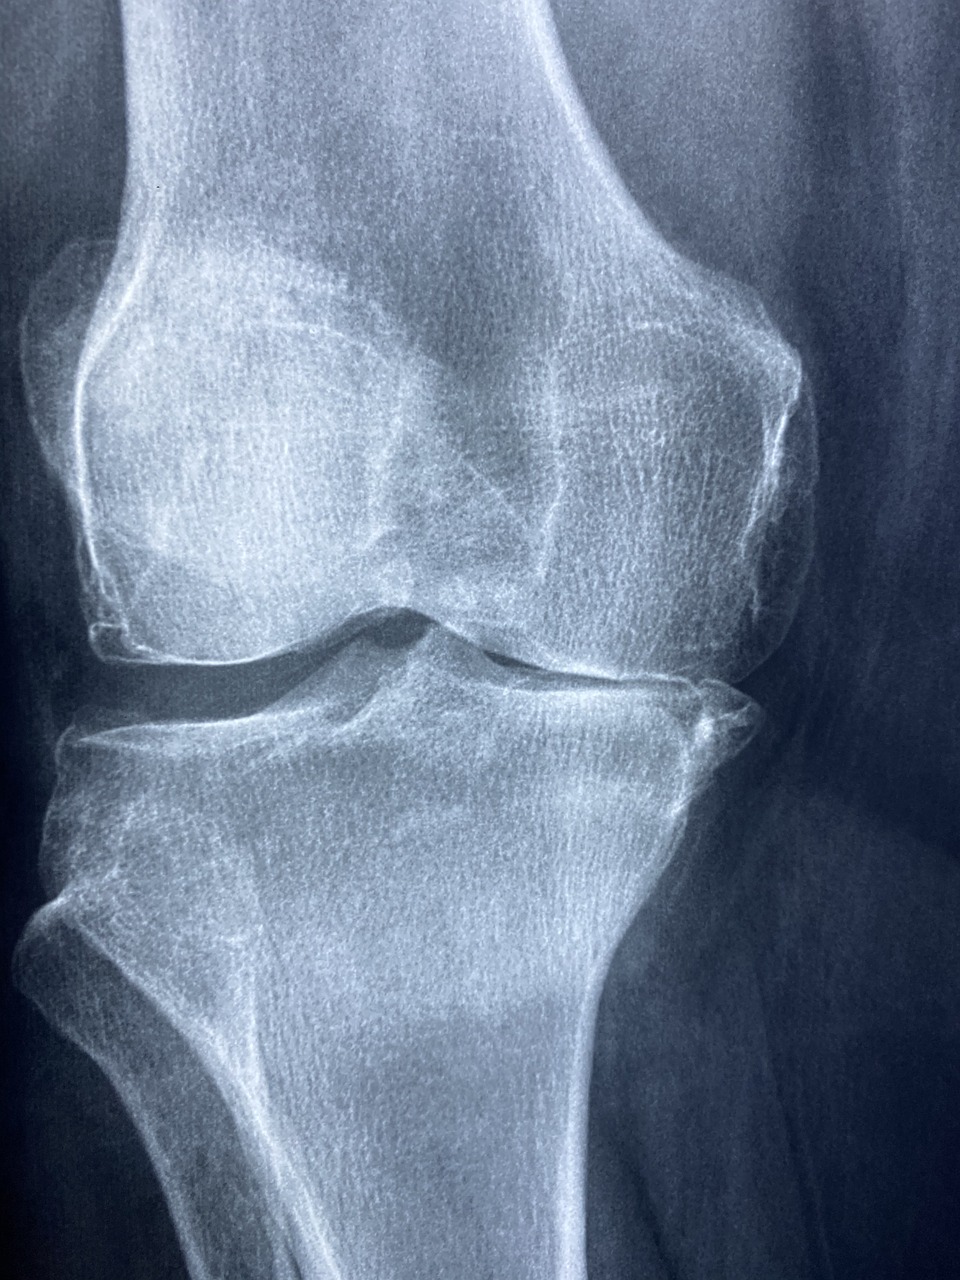

1. 퇴행성 관절염

가장 흔한 무릎 통증 원인입니다.

나이가 들면서 연골이 점차 닳고, 관절 사이가 좁아지면서 통증, 붓기, 관절 마찰음이 발생하죠.

초기에는 무릎을 움직일 때 뻣뻣함만 느껴지지만, 진행되면 앉았다 일어설 때 찌릿한 통증이 동반됩니다.

병원 치료 요령과 의료기관 선택 팁

- 정형외과 중 ‘관절 전문 클리닉’ 보유 병원 선택

- MRI 촬영 여부, 물리치료 시스템 확인

- 만성 통증은 단순 X-ray로 확인이 어려운 경우 많으므로

무릎 통증이 2주 이상 지속된다면 전문 진료를 받는 것이 좋습니다.